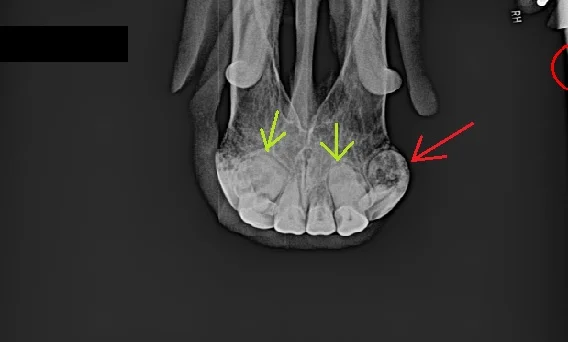

X-ray of a horse with EOTRH. The green arrows point to bulbous roots (hypercementosis) and the red arrow points to a tooth with both hypercementosis and resorption (the black area inside the tooth).